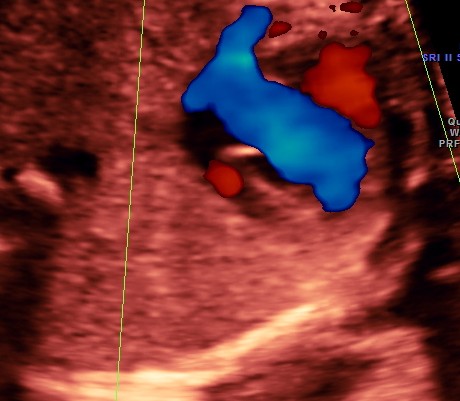

the following video shows right atrium and rt ventricle to be grossly dilated and the left atrium and left ventricle to be very small and hypoplastic.